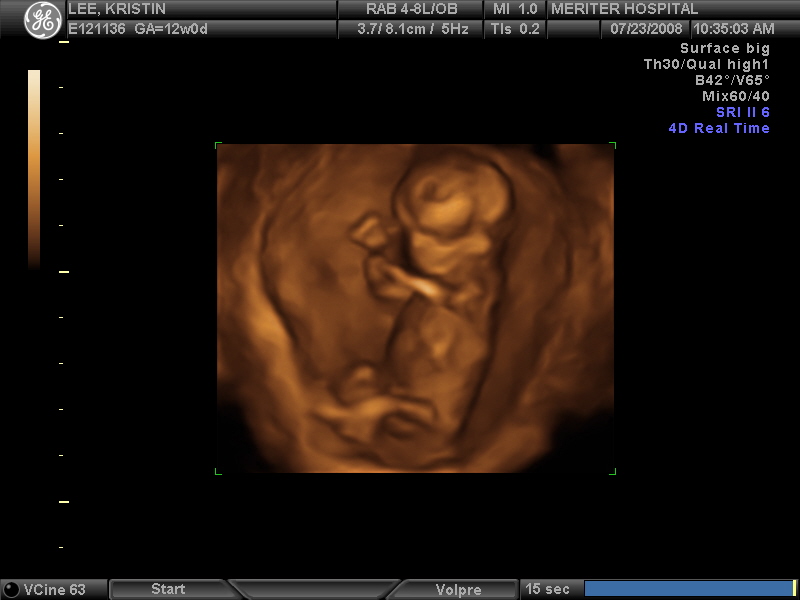

Ultrasound

February 2nd, 2009